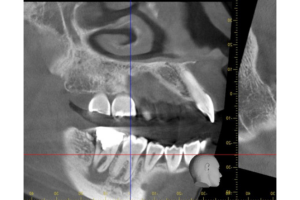

基本情報

| 年齢・ 性別 |

30歳・女性 |

|---|---|

| 主訴 | 主訴:他院で2年程前に入れたジルコニアクラウンが痛む。 ジルコニアクラウンを入れた時にかみ合う上の歯を大きく削られたが、かみ合わせにずっと違和感もある。 部位:右下7番 |

| 治療 内容 |

被せ物を除去しかみ合わせを確認。 再根管治療を行い、根管治療後土台(FBコア)まで入れたらかみ合わせを高さを確保するために歯ぐきを下げる処置(CLP)を行い、経過を診た後に被せ物の型取りをしました。 |

| 治療 期間 |

約6ヶ月 |

| 治療費 | 合計:135,000円 右下7番 ファイバーコア 16,500円 ジルコニアクラウンステイニング無 60,500円 CLP 55,000円 CT算定代約3,000円 (2024年10月現在) |

| リスク・副作用 | ・かみ合わせの高さが高い、きついなどの違和感を被せ物セット後すぐは違和感を覚えることがありますが、1週間程度で慣れて気にならなくなってきます。 ・破折や脱離のリスクを下げるためにもナイトガード(マウスピース)のご使用をお願いしています。 |

| 治療方針 | 他院で入れたジルコニアクラウンの為どのような状態なのかを確認するためにCT撮影して精査しました。 きちんと根充剤が入っていない部分があり、根の部分全周にかなり大きい膿が出来ていました。かみ合う上の歯と当たってしまうことで膿に刺激がいき痛みが出ている状態でした。 被せ物を外して咬合確認したところ、被せ物が高かったようで、外したら本来の正常なかみ合わせになり顎関節の違和感も解消されました。土台も外して再根管治療を行いました。 根管治療中も顎関節の経過を診ながら治療を進めました。 再根管治療後、土台を入れた後に被せ物を入れるスペースを確保するために、歯ぐきを下げる処置を行い経過を5ヶ月程度みました。 顎関節の違和感が解消され、レントゲン撮影し透過像の縮小、治癒がみられたので、被せ物の型取りを行い被せ物をセットしました。 |